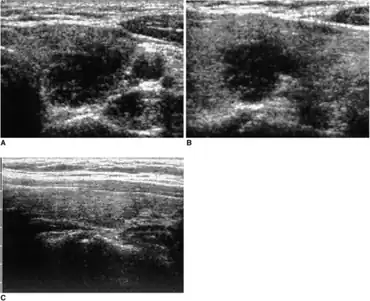

| Micrograph showing a granuloma in subacute thyroiditis. H&E stain. | |